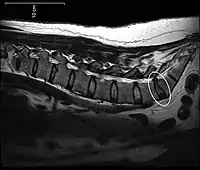

![]() Протрузія диска на МРТ Протрузія диска на МРТ | |

Багато аномалій диска, які видно на МРТ, й умовно іменуються «грижа», насправді просто випадкові знахідки. Вони можуть просто потовщеннями фіброзного кільця. Jensen і його колеги, які проводили МРТ-дослідження поперекового відділу хребта 98 безсимптомних випадків у дорослих, виявили, що більш ніж у половини з досліджених було симетричне випучування диска (або декількох дисків). У 27 відсотків, було виявлене центральне або асиметричне розширення диска (протрузія), і тільки в 1 відсотку було виявлене екстремальне розширення диска (екструзія, секвестр). Ці результати підкреслюють важливість використання більш точних термінів при описі візуалізації аномалій та оцінки їх строго в контексті симптоматики пацієнта.[3]